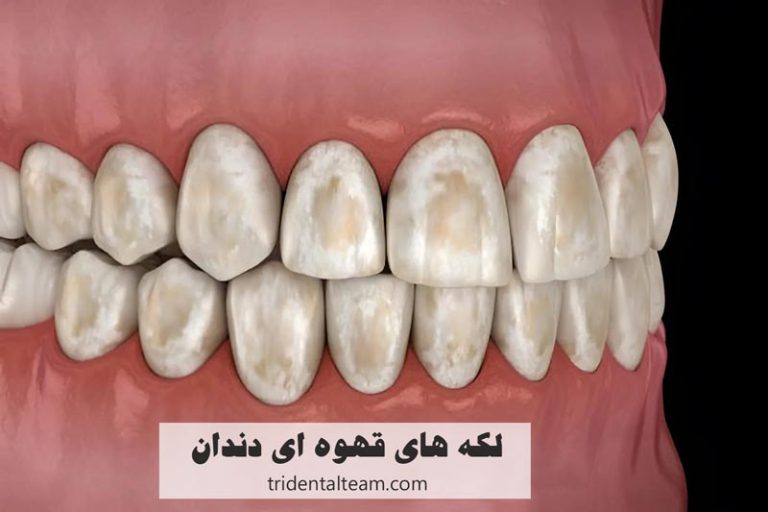

افرادی که دچار تجمع پلاک و جرم روی دندان ها شده اند، کسانی که علائم اولیه التهاب لثه مانند خونریزی هنگام مسواک زدن یا بوی بد دهان دارند، افرادی که به سلامت دهان و زیبایی لبخند خود اهمیت می دهند و کسانی که دارای رنگ گرفتگی سطحی دندان ها به دلیل مصرف چای، قهوه یا سیگار هستند، کاندیدای مناسب جرم گیری دندان به شمار می روند و با انجام این روش می توانند سلامت لثه ها و درخشندگی دندان های خود را حفظ کنند. این افراد شامل موارد زیر می شوند:

- تغییر رنگ دندان ها (زرد یا قهوه ای شدن)

| تغییر رنگ دندان | تجمع پلاک و جرم باعث تیرگی و لکه های روی دندان می شود. |

جرم گیری دندان در اصل یک روش درمانی و پیشگیرانه برای برداشتن پلاک ها و رسوبات سخت شده روی دندان ها و لثه ها است. این فرآیند می تواند رنگ گرفتگی های سطحی ناشی از مصرف نوشیدنی هایی مانند چای، قهوه یا سیگار را تا حد زیادی از بین ببرد و دندان ها را تمیزتر و براق تر نشان دهد. با این حال، جرم گیری یک روش سفیدکننده به معنای واقعی نیست و رنگ طبیعی دندان ها را تغییر نمی دهد، بلکه فقط جرم و لکه های سطحی را پاک می کند.

- دندان های سفید و درخشان: ایجاد لکه بر روی دندان ها به خاطر خوردن و نوشیدن انواع مواد غذایی و نوشیدنی های رنگی اجتناب ناپذیر است، به ویژه اگر قهوه بنوشید یا تنباکو مصرف کنید. جرم گیری منظم دندان به شما اعتماد به نفس میدهد تا هر بار که میخندید، دندان های درخشان خود را به نمایش بگذارید!